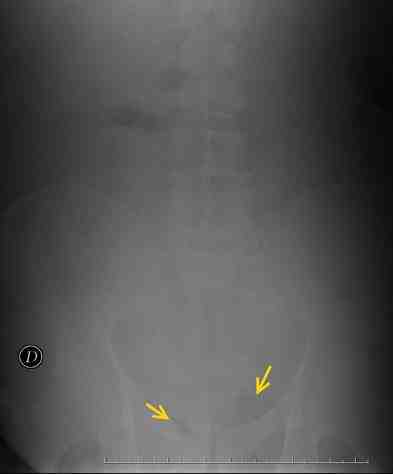

Caso 4: Varón de 51, años con antecedentes de DM tipo II, obesidad y hepatopatía crónica con hipertensión portal secundaria. Acude a urgencias por cuadro de malestar general y fiebre. Como estudio de imagen se realiza Rx simple de abdomen (figura 4), no informada. En exploración física se refiere necrosis grasa anorrectal, con diagnóstico de gangrena de Fournier se interviene de forma urgente. Tras alta reingresa por nuevo cuadro requiriendo reintervención, varias curas, estancia de 7 días en UCI y transfusiones. Dado de alta tras lenta recuperación en planta.

Figura 4: En revisión de Rx simple de abdomen puede apreciarse acumulo de gas en localización anómala a nivel isquiorrectal, consistente con su diagnostico conocido de gangrena de Fournier.